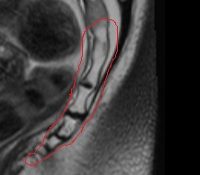

Магнитный резонанс копчика Неинвазивный метод сканирования слоя за слоем нижней части позвоночника с использованием электромагнитного поля с последующей фиксацией данных, полученных с помощью специального оборудования. Он используется для визуализации костей копчика и окружающих мягких тканей, нервов, кровеносных сосудов. Используется для диагностики воспалительных и деструктивных изменений в костях и тканях, окружающих кости копчика. Предназначен для выявления посттравматических переломов и патологий, структурных аномалий, различных типов объемных образований Методика использовалась при подготовке пациентов к операциям на тазовой области. Возможно, МРТ-сканирование копчика с контрастностью и без нее, специальной подготовки к исследованию не требуется.

МРТ сoccyx основана на свойстве атомов водорода в клетках организма изменять свою полярность под воздействием электромагнитных волн в постоянном магнитном поле. Изменения регистрируются датчиками томографа и передаются на специальный компьютер в виде изображений отдельных слоев. Этот метод используется в диагностике со второй половины 20-го века и является одним из приоритетов при углубленном осмотре нижней части позвоночника. МРТ-копчик позволяет получать изображения с высоким разрешением, которые позволяют выявлять опухоли на ранних стадиях, а также выявлять хронические переломы копчика, которые часто отсутствуют в обычной рентгенографии.